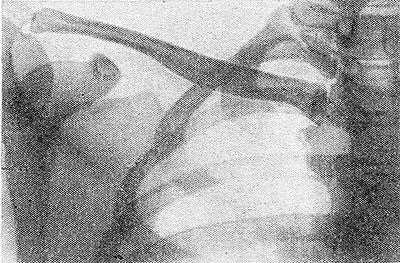

Рис. 1. Ключично-черепной Дизостоз (синдром Шейтхауэра—Мари—Сентона) у трех сестер. Отсутствие ключиц у двух сестер приводит к полному соприкосновению плеч.

Ключично-черепной Дизостоз (синдром Шейтхауэра — Мари — Сентона) характеризуется гипоплазией покровных костей черепа в сочетании с полным или частичным недоразвитием одной или обеих ключиц, т. е. нарушением развития так наз. мембранозных костей. Для Д. этого вида характерно незаращение или позднее заращение черепных швов и родничков, брахицефалия (см.) с преобладанием расширения свода черепа в латеральных направлениях, выдающийся лоб, гипоплазия лицевых костей, гл. обр. верхней челюсти, обусловливающая псевдопрогению (кажущееся увеличение нижней челюсти). Нарушение развития челюстей сопровождается запаздыванием прорезывания зубов. Отсутствие ключиц или частичное недоразвитие их с дефектом внутренних, средних или наружных частей ведет к увеличению подвижности плечевого пояса, а при полном отсутствии их — к полному соприкосновению плеч (рис. 1).